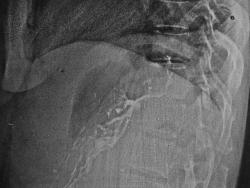

Ничего не имею против серомы в принципе, но все-таки в конкретном случае, откуда в этой полости следы бария, они-же явно виды (я отметил стрелками)?

Просто свод желудка это осумкованное скопление с трех сторон окутал, и прямой и боковой с барием сделаны одновременно, друг за другом, и в прямой проекции хорошо видно, что барий туда не заходит. А в боковой - наложение проекционное.